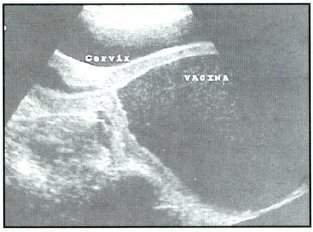

Fig: 2 Hematocolpos

La paciente es operada con el diagnóstico de tabique vaginal transverso incompleto a pesar de no demostrarse solución de continuidad en la vagina. Los reportes ecográficos y TAC reportaron hematometra gigante con hematocolpos y presencia de posible tabique vaginal en 1/3 inferior de vagina, que coincide con el examen físico que mostraba un tabique vaginal completo (Fig: 1,2,3,4).